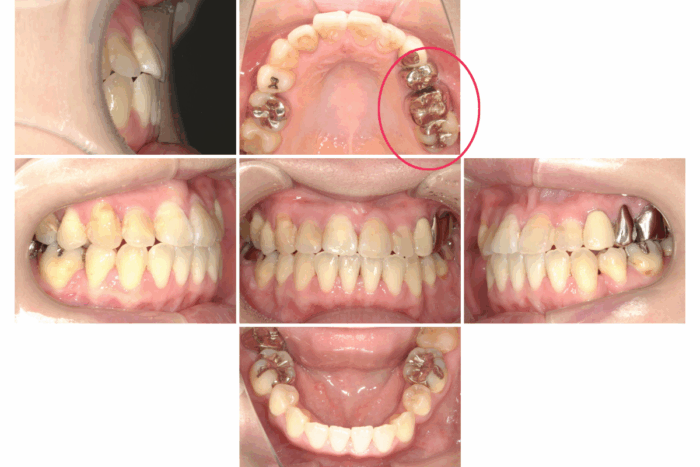

患者さま:30代女性/左上4・5・6番にメタルブリッジ

主訴:歯のガタつき・かみ合わせが反対

矯正治療のために上下左右4本抜歯する必要がありました。そのため、抜歯する歯のうち1本は、ブリッジを分割しポンティック部分(ブリッジの真ん中の人工歯のこと)を除去して代用しました。ワイヤー矯正で歯並びとかみ合わせを改善しました。

- 【症例詳細】

- 主訴:ガタガタと受け口が気になる

- 診断名:叢生・反対咬合

- 初診時年齢:32歳

- 使用装置:ホワイトワイヤー矯正

- 抜歯部位:上顎右側第二小臼歯、下顎右側第二小臼歯、下顎左側第一小臼歯

- 治療期間:2年7ヶ月

- 費用:¥750,000(税込¥825,000)

- リスク・副作用:痛み、歯根吸収、歯肉退縮、むし歯、後戻り